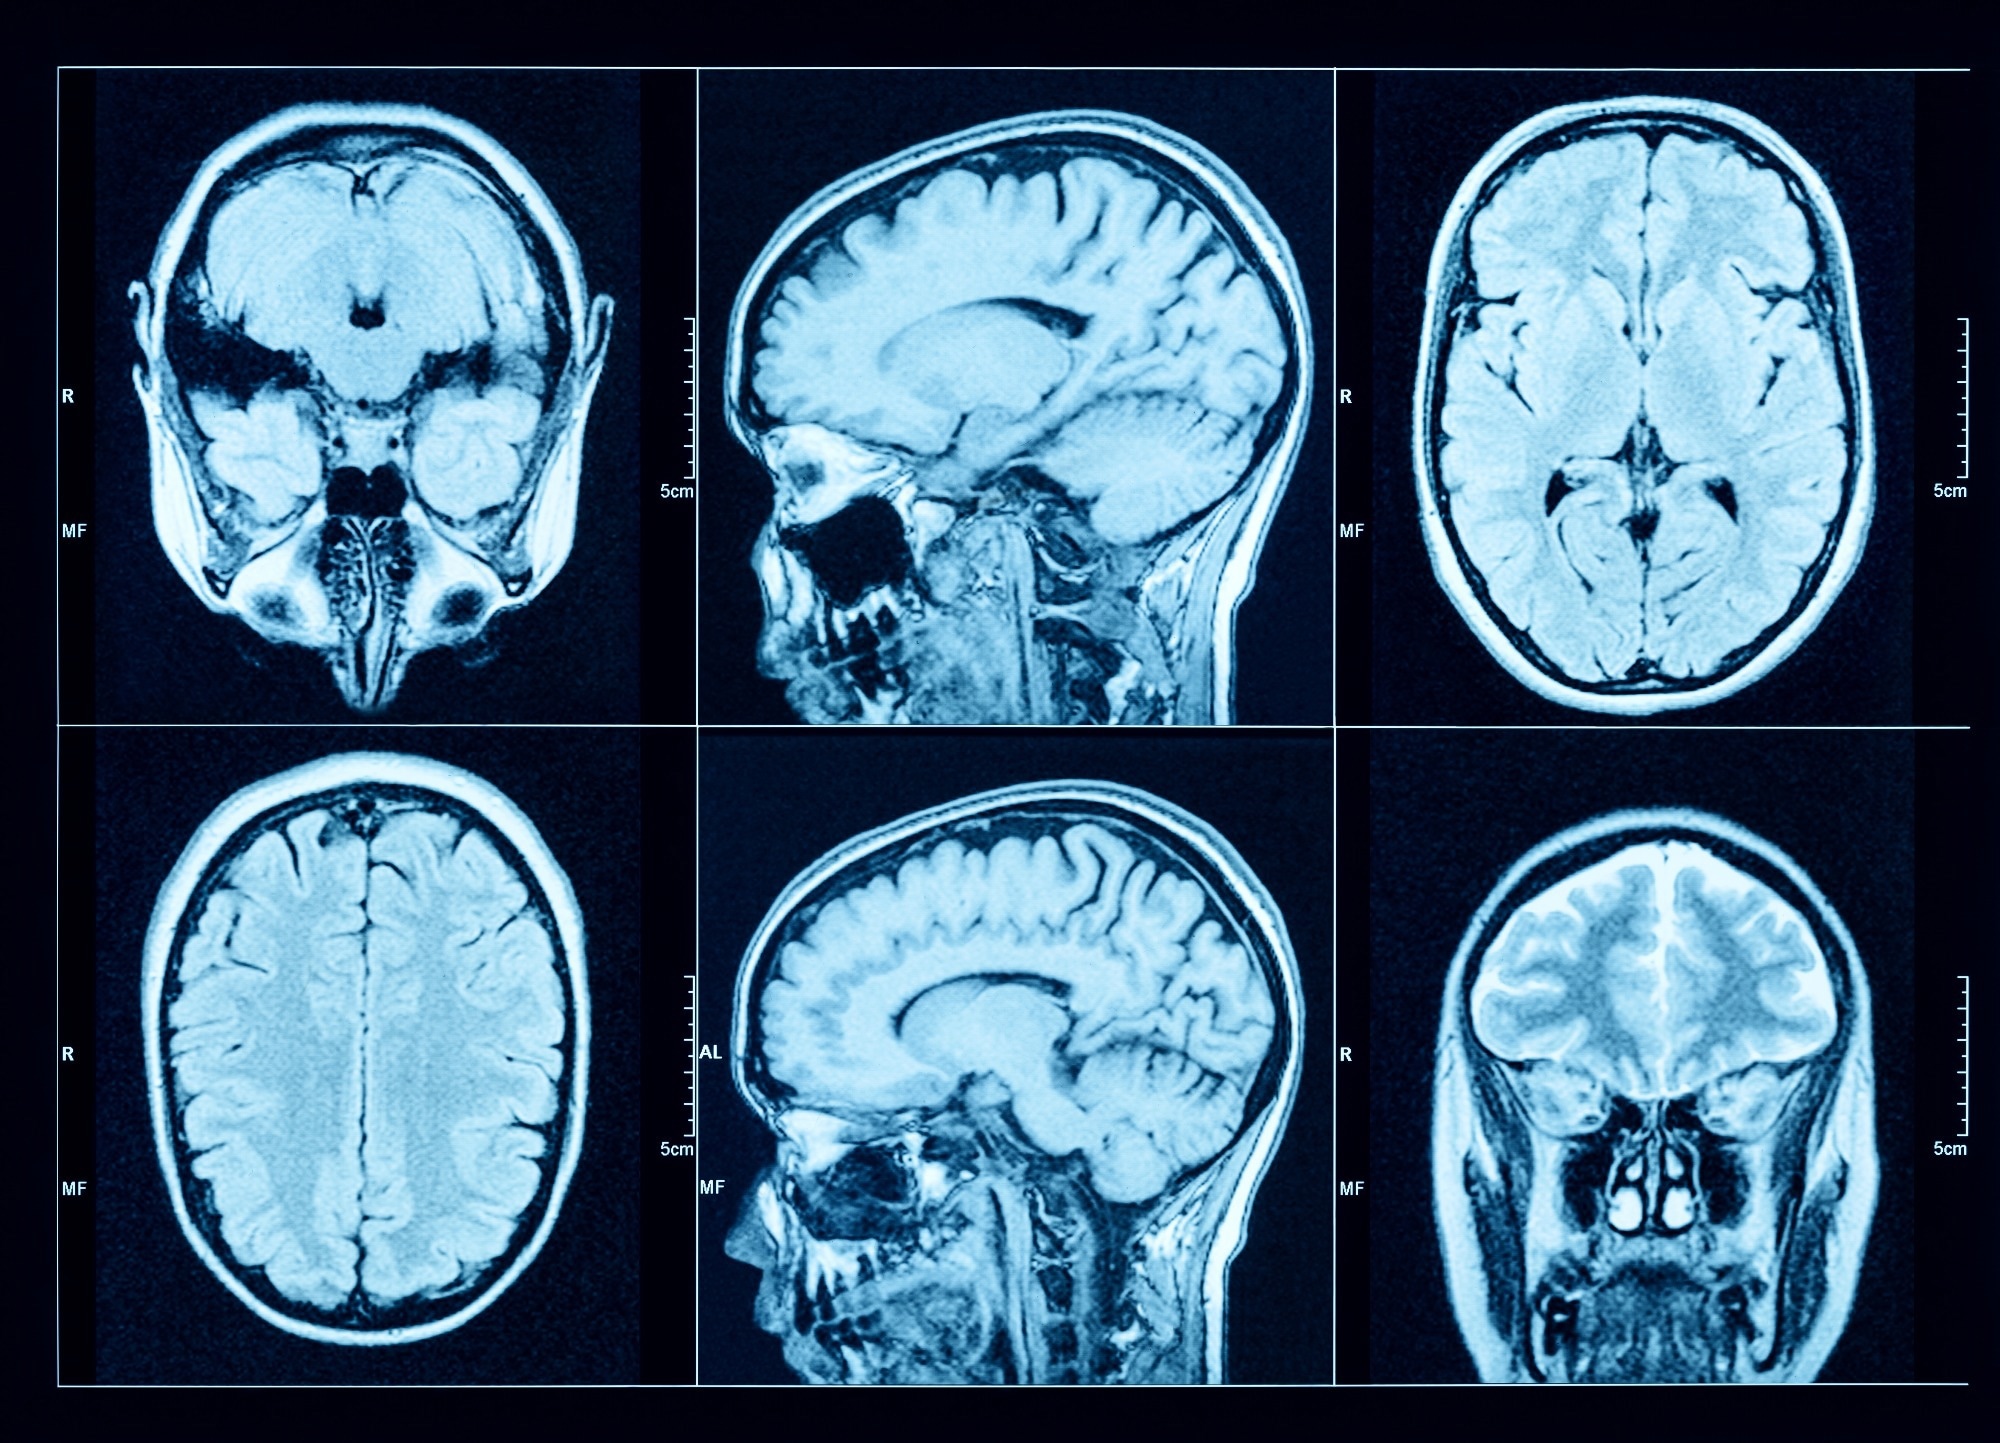

Study: Association of gout with brain reserve and vulnerability to neurodegenerative disease. Image Credit: Triff / Shutterstock.comStudy: Association of gout with brain reserve and vulnerability to neurodegenerative disease. Image Credit: Triff / Shutterstock.com

Study participants were recruited from the United Kingdom Biobank (UKB) study, which enrolled 40 to 69-year-old volunteers between 2006 and 2010. A subset of these patients underwent imaging, including magnetic resonance imaging (MRI) of the brain.

The team utilized 2,138 summary image-derived phenotypes (IDPs) that represented different estimates of brain structure using T1-weighted and T2-weighted-FLAIR structural imaging, diffusion MRI, and susceptibility-weighted MRI. FMRIB software library voxel-based morphometry (FSL-VBM) was used to determine the precise spatial distribution of relationships between gout and gray matter volume throughout the brain.

MRI results were used to determine whether causal relationships could explain the observed associations with brain structure. One-sample (gout) and two-sample (urate) linear MRI assessments utilizing summary statistics obtained from European participants were also performed.